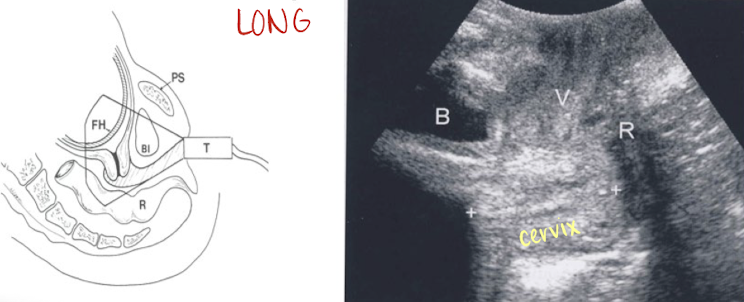

cervix: transabdominal technique

scan through amniotic fluid/bladder to image cervix

measure length of cervix from internal os to external os

do not include vaginal canal in measurement

pitfalls:

maternal body habitus

full bladder can compress LUS and mimic a long closed cervix